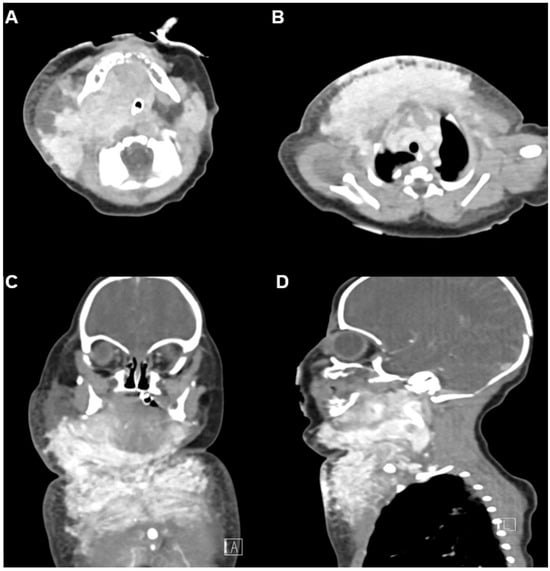

Neonatal Kaposiform Hemangioendothelioma with Kasabach–Merritt Phenomenon Presenting as Severe Airway Obstruction at Birth: A Case Report

Background/Objectives: Kaposiform hemangioendothelioma (KHE) is a rare, locally aggressive vascular tumor of infancy, often complicated by Kasabach–Merritt phenomenon (KMP), a consumptive coagulopathy characterized by severe thrombocytopenia and hypofibrinogenemia. Airway involvement at birth is exceptionally rare and can be life-threatening. This study reports [...] Read more.

Background/Objectives: Kaposiform hemangioendothelioma (KHE) is a rare, locally aggressive vascular tumor of infancy, often complicated by Kasabach–Merritt phenomenon (KMP), a consumptive coagulopathy characterized by severe thrombocytopenia and hypofibrinogenemia. Airway involvement at birth is exceptionally rare and can be life-threatening. This study reports the clinical presentation and treatment course of a full-term male neonate with severe airway obstruction caused by KHE with KMP. Case Presentation: The patient had unremarkable prenatal imaging but presented at birth with severe respiratory distress requiring emergent intubation. Physical examination revealed firm violaceous swelling over the right cervicothoracic region. Laboratory tests showed profound thrombocytopenia (22,000/μL), hypofibrinogenemia (75 mg/dL), and coagulopathy. Imaging findings were consistent with KHE complicated by KMP. Due to bleeding risk, the biopsy was not performed. Initial treatment included platelet and plasma transfusions, intravenous immunoglobulin (IVIG), corticosteroids, and antithrombin III replacement. Vincristine was discontinued owing to gastrointestinal toxicity. Sirolimus therapy was initiated on day 14. Following sirolimus initiation, rapid platelet recovery was observed. At three months, marked tumor regression was documented. After mild recurrence, sirolimus was reintroduced, and the patient remained stable at 16-month follow-up. Conclusions: This case underscores the critical importance of prompt airway stabilization, early recognition of consumptive coagulopathy, and sirolimus-based therapy in managing neonatal KHE with airway involvement. Full article

Show Figures

Figure 1